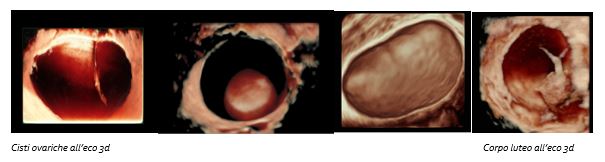

Ecografia ginecologica tridimensionale

Che cos’è

L’ecografia tridimensionale consente di studiare contemporaneamente un determinato settore dell’organo interessato sui tre piani ortogonali e di ricostruirne un volume. È indicata in tutti in casi in cui una semplice ecografia di primo livello non sia in grado di fornire un adeguato inquadramento diagnostico di una paziente o nel caso in cui sia necessario raccogliere dati aggiuntivi, non ricavabili da una tecnica di base.

- Ecocolor Doppler bi-tridimensionale: consente di visualizzare e studiare il decorso dei vasi e delle ramificazioni vascolari degli organi genitali interni sia in condizioni fisiologiche che patologiche, fornendo un ulteriore criterio differenziale tra formazioni benigne, borderline e maligne.

In oncologia è difatti fondamentale riuscire ad inquadrare in fase pre-operatoria una lesione in maniera precisa e dettagliata in modo da poter eseguire successivamente un intervento mirato ed adeguato; è in questa fase che l’ecografia di secondo livello si distingue per sensibilità e specificità stadiativa. Vi è in letteratura una forte evidenza che la valutazione soggettiva di una massa ovarica effettuata da un operatore dedicato attraverso l'ecografia sia un ottimo metodo per discriminare tra benignità e malignità ed in molti casi può essere suggerita pure una corretta diagnosi di natura della neoplasia sulla base della sola ecografia che, se associati alla clinica, all'esecuzione dei marcatori ovarici, aumentano ulteriormente la sensibilità nella diagnosi e nella stadiazione preoperatoria.